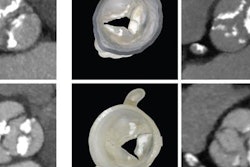

The computed axial lithography method resembles 3D CT scanning in reverse, because it estimates what 2D images (or images slices) of a 3D model might look like from many different angles and then feeds these 2D images into a projector, senior author Hayden Taylor, PhD, from the University of California, Berkeley, and colleagues wrote in a January 31 report in Science.

Thus far, the researchers have been able to create centimeter-scale 3D-printed models in less than two minutes. They believe their technique is more flexible than conventional 3D printing because, for instance, it allows users to create objects that enclose existing ones.